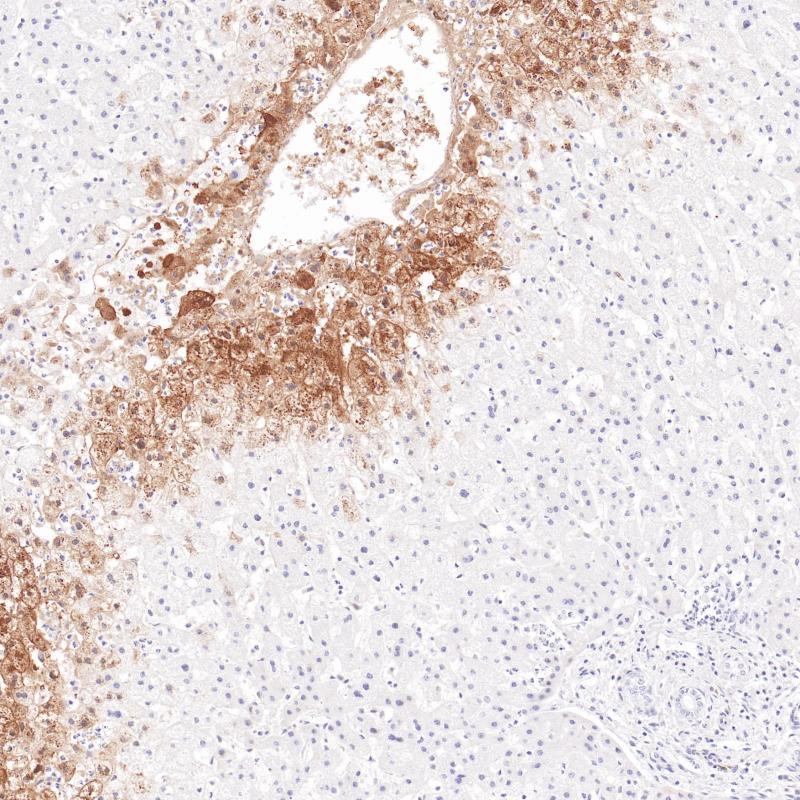

MHC II(DRα chain) 重组兔单克隆抗体

主要组织相容性复合体 II 类(MHC II 类)分子是在巨噬细胞、树突细胞和 B 细胞等抗原呈递细胞表面表达的异二聚体的跨膜糖蛋白。在人体中,MHC II 类蛋白复合体被人白细胞抗原基因复合体 (HLA) 编码。MHC II可在 B 淋巴细胞、活化的 T 淋巴细胞、活化的自然杀伤 (NK) 细胞等表达。

阳性对照

食管